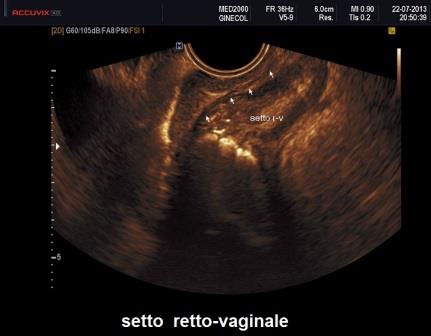

I noduli interessanti la parete vaginale e il setto retto-vaginale si presentano come noduli ipoecogeni, irregolari, accompagnati ad ispessimento della parete vaginale.

Si presentano come noduli ipoecogeni con contorni iperecogeni irregolari e sfumati, fissi e dolenti alla pressione con la sonda vaginale, scarsamente vascolarizzati al power Doppler; inoltre questi noduli provocano delle tipiche distorsioni delle strutture anatomiche coinvolte che danno origine a patterns ecografici caratteristici delle diverse localizzazioni.

La localizzazione intestinale è frequentemente appannaggio del retto e della giunzione rettosigmoidea. E' di fondamentale importanza riconoscere la struttura normale della parete intestinale: la tunica muscolare ha un aspetto ipoecogeno mentre sottomucosa e mucosa hanno aspetto iperecogeno. L'interessamento intestinale è caratterizzato dalla presenza di un nodulo ipoecogeno posteriormente all'utero e adeso alla parete anteriore dell'intestino; in genere è interessata la porzione muscolare della parete intestinale; se il nodulo interessa anche la sottomucosa e la mucosa si ha una interruzione della rima iperecogena che le contraddistingue ecograficamente, anche se l'interessamento della mucosa è spesso impossibile da diagnosticare. Il decorso del retto e del sigma può essere distorto e la retrazione fibrosa delle anse intestinali verso il nodulo posto in zona retrocervicale crea multiple pliche che danno origine ad un segno ecografico caratteristico denominato "cappello da indiano" "indian headdress sign". Al power Doppler vi è una scarsa vascolarizzazione sia interna che periferica del nodulo. La maggior parte di questi noduli obliterano il cavo del Douglas per cui è possibile valutare, mediante la pressione con la sonda endovaginale, lo scivolamento tra retto e parete posteriore dell'utero "sliding sign". Un'altro segno è quello di evocare dolore mediante la pressione con la sonda endovaginale sulle strutture da studiare "tenderness-guided ultrasonography".

L'interessamento dei legamenti utero-sacrali e del torus uterino è caratterizzato dalla presenza di noduli ipoecogeni a margini stellati, profili esterni irregolari, scarsamente vascolarizzati al power Doppler e adiacenti alla cervice uterina; in genere l'interessamento dei legamenti utero-sacrali è rappresentato ecograficamente da un ispessimento dei legamenti piuttosto che dalla chiara presenza di un nodulo. La diagnosi è facilitata confrontando simultaneamente i due lati al fine di individuare anche la presenza di un nodulo unilaterale; in questi casi è di aiuto l'asimmetria e l'irregolarità dei profili dei legamenti piuttosto che lo spessore del nodulo. Importante valutare la mobilità ed il dolore evocato dai movimenti e dalla pressione con la sonda endovaginale.